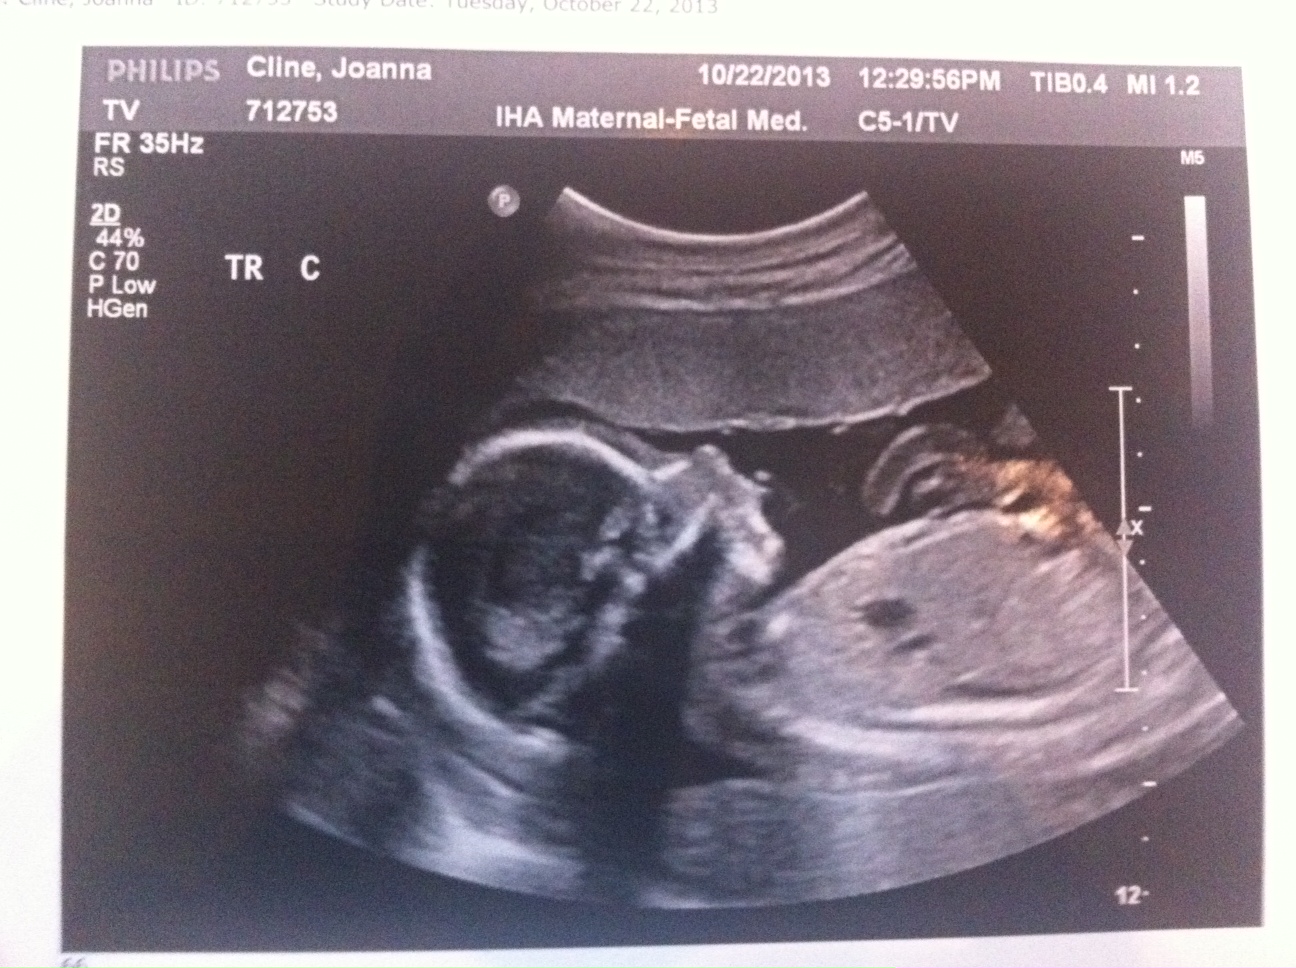

Everything still looks great. The triplets are growing but we won’t have another growth scan until my 22wk appointment. Heart beats look good and it’s clear they’re getting bigger (Today’s pictures attached.)